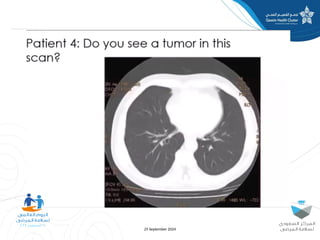

The document discusses diagnostic errors, particularly focusing on cognitive biases and their impact on decision-making in healthcare. Dr. Asmaa Fayez emphasizes the importance of recognizing and mitigating these biases to avoid human errors that can lead to serious incidents. The presentation highlights the urgent need for timely interventions in the context of patient safety.